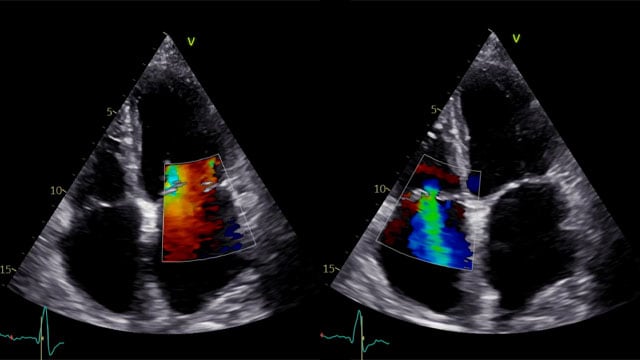

Multimodality imaging reveals fibro-calcific leaflet disease, restricted motion, and a short posterior leaflet, making him a suboptimal candidate for M-TEER and prompting consideration of transcatheter mitral valve replacement. How would you treat?